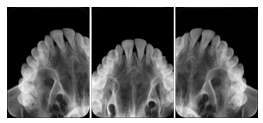

OO.1.2 Ophthalmology

1. A patient in rural Canada visits a general ophthalmologist and is found to have diabetic macular edema. The general ophthalmologist would like to discuss the case with a retina specialist before performing laser surgery. A fluorescein angiogram is done with multiple retinal images taken in a timed series after an intravenous injection. The images along with a Structured Display are shared via a Health Information Exchange with a retina specialist in Calgary, who opens them using his Ophthalmology EMR software and consults via phone with the general ophthalmologist. Both physicians view the images in the same layout so the retina specialist can provide accurate guidance for treating the patient.

2. A patient in rural Iowa visits his primary care physician for management of diabetes. Three non-mydriatic (patient's eyes are not dilated) photographs are taken of the back of each eye, and forwarded electronically along with a Structured Display to an ophthalmologist in Iowa City. The ophthalmologist reads the photos in an agreed upon layout so there is no mistake about what portion of which eye is being viewed. The ophthalmologist is able to tell the primary care physician that his patient does not need to come to Iowa City for face to face ophthalmologic care, but that there is a particular view of the left eye that should be photographed again in 6 months.

Ophthalmic Retinal Study Structured Display

Figure OO-3. Ophthalmic Retinal Study Structured Display